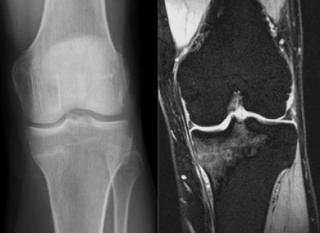

Что показывает МРТ коленного сустава

МРТ коленного сустава (МРТ колена) считается одним из самых надежных медицинских исследований, позволяющих оперативно выявить большинство проблем с коленными структурами. Коленный сустав часто

МРТ или КТ коленного сустава

МРТ или КТ коленного сустава - это два высокоэффективных метода диагностики организма человека, а вот какой из них и в чем лучше, давайте попробуем разобраться. В зону колена входят ткани разного характера: костные ткани - бедренная кость, малая и большая берцовая кость, хрящи суставной поверхности, мениски; мягкие ткани - связки, мышцы сухожилия, сосудисто-нервные пучки, жировое тело. Из-за физики получения изображения кость лучше всего визуализируется на